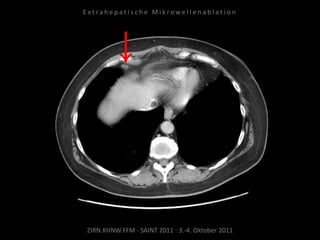

Patient: Weiblich, 71 Jahre

Diagnose: Ovarial-Ca,

größenprogredienter Lymphknoten

zwischen Herz und Leber als einzige

Metastase.

Situation:

Nur 1 Metastase, diese ist jedoch

progredient. Kritische Lage in

Herznähe.

Indikation zur MWA:

Nachweis nur einer Metastase, diese

ist progredient, in der Größe gut zur

Ablation geeignet.

Ablation am 24.03.2010:

2 Nadelpositionen.